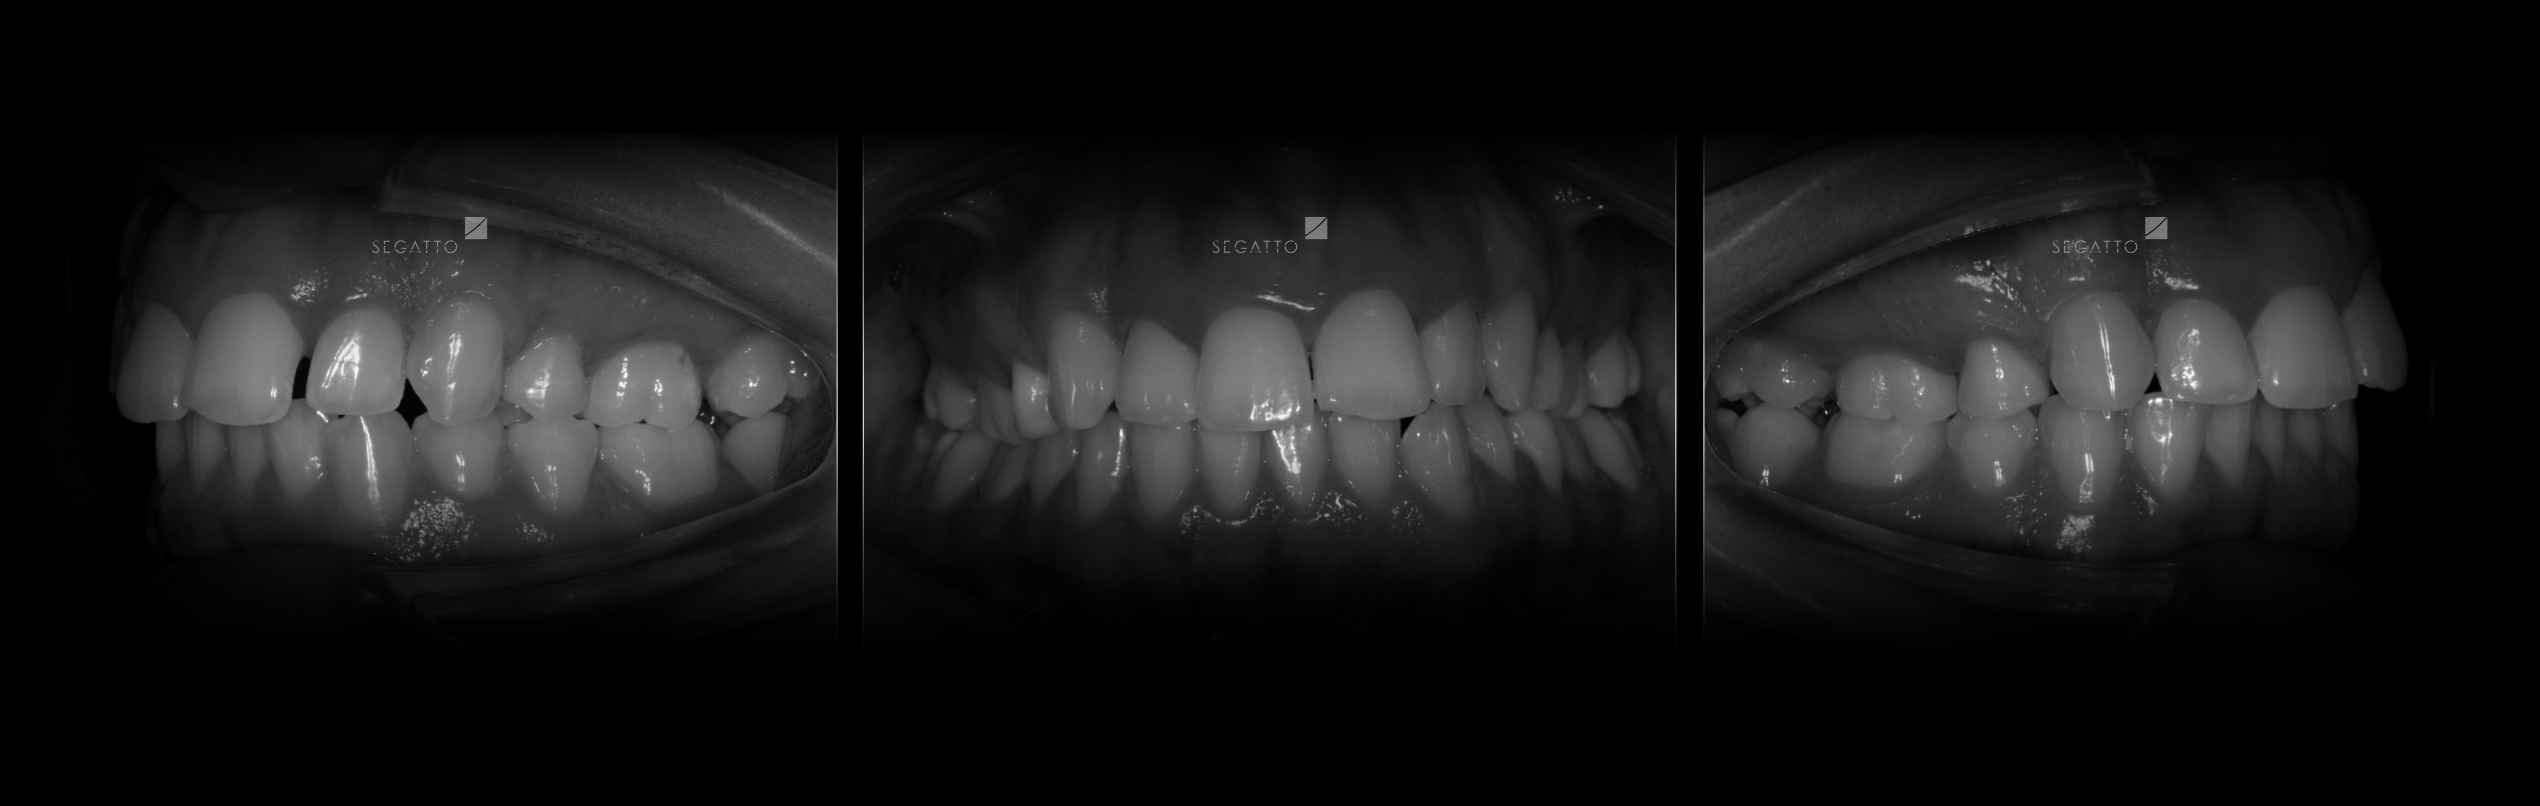

Orthodontics

Cases